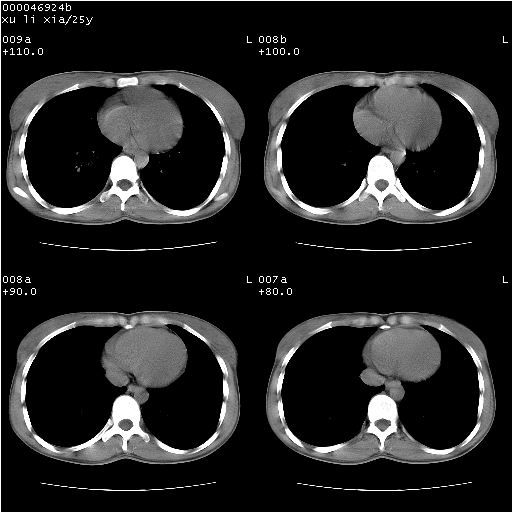

患者 女,25岁。因“左侧卵巢肿瘤”术前胸片偶然发现两肺病变。平素无明显不适,无呼吸系统症状及体征,无传染病史。

胸部ct轴位平扫(层厚10mm,螺距1.5,重建间隔10mm),图像如下:

双肺病灶以渗出影搀杂斑点状阴影为主,部分阴影融合成团片,并沿纹理明显见播散灶。支持楼主:两肺感染性病变(结核可能性大)!

双肺上叶可见节段性渗出性病变,可见树芽征像,左肺下叶背段可见结节影。

平行于间质走行微结节影;拌钙化灶;分布通气好的肺野